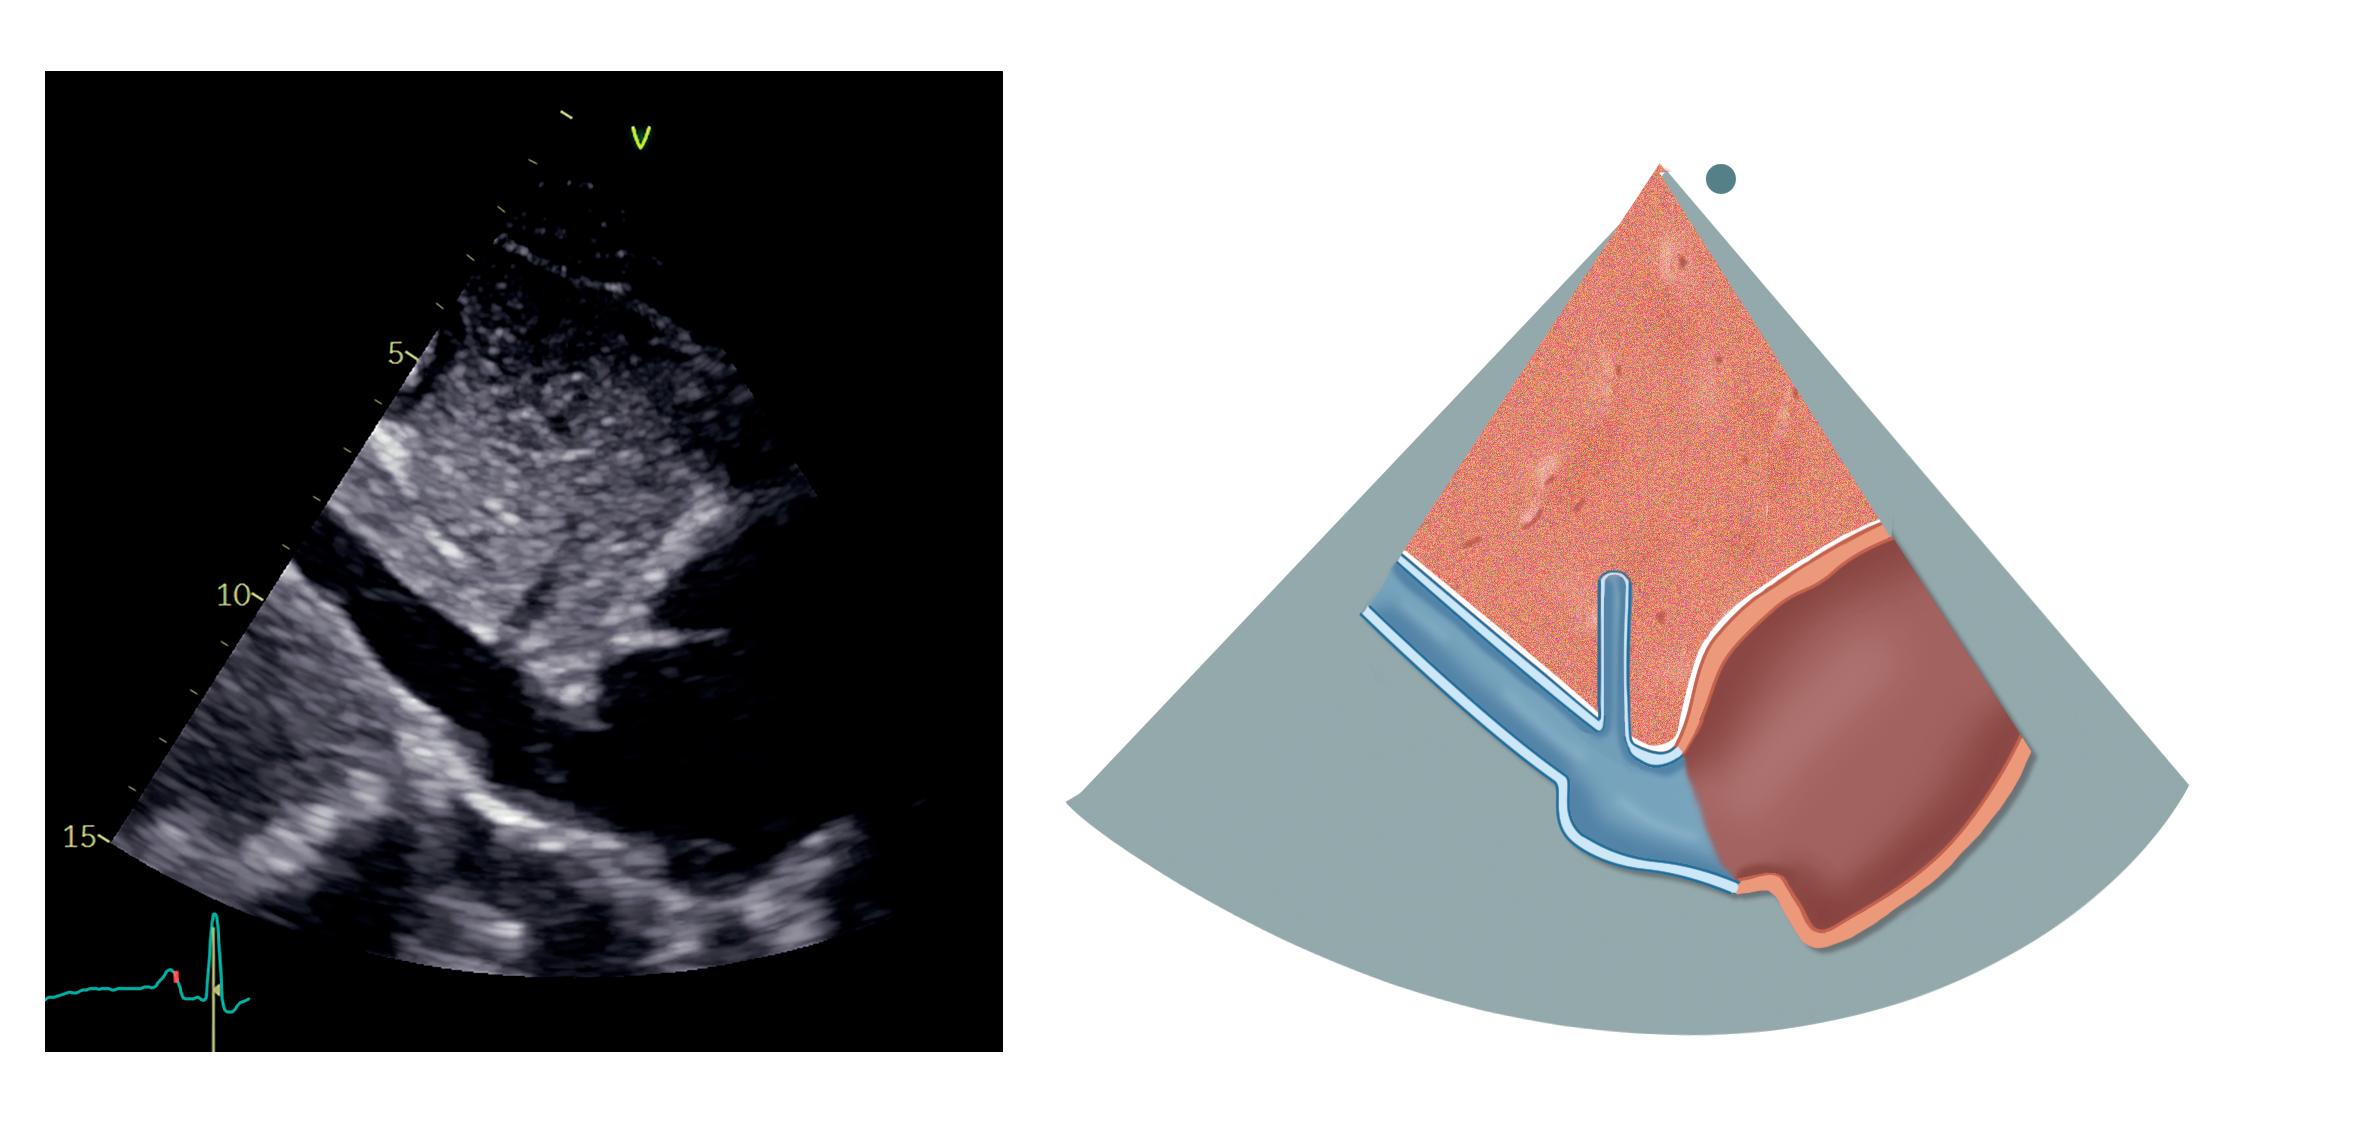

I denne projeksjonen ses hjertet i langakse fra venstre (figur 2.2).

Subkostal Høyre parasternal Figur 2.1: De ulike projeksjonene og plasseringen av transduseren ved TTE Mitralkla en (MK) Venstre atrium (VA) Venstre ventrikkel (VV) LVOT Aortakla en (AK) Ventrikkelseptum (IVS) Høyre ventrikkel (HV) IVS HV LVOT VV MK VA AK Figur 2.2: Parasternal langakseprojeksjon

Øverst i bildet, anteriort mot transduseren, ligger høyre ventrikkels utløpstraktus (RVOT). Posteriort for den ligger venstre ventrikkel med anteriore septum og inferolaterale (også kalt posteriore) vegg. Ventrikkelens lengdeakse skal ligge horisontalt i bildet, og apex skal som regel ikke være synlig, ellers har vi vinklet transduseren feil. Videre ses venstre atrium nede til høyre i bildet, og hos noen kan aorta descendens i kortakse visualiseres posteriort for atriet. Sinus coronarius kan ses i bakkant av atriet nede ved atrioventrikulærovergangen, men er knapt synlig med mindre den er dilatert.

Venstre ventrikkels utløpstraktus (LVOT) og aortaklaffen skiller venstre ventrikkel og aorta ascendens. To av klaffens tre kusper er synlige: Anteriort ligger den høyre koronare kuspen, mens den posteriore vanligvis er den non-koronare kuspen – men man er så nær kommissuren mot den venstre koronare kuspen at man unntaksvis kan visualisere eller gjennomskjære denne. Aortaroten med sinus Valsalvae, den sinotubulære overgangen og proksimale aorta ascendens ligger til høyre i bildet. Et tips for å visualisere mer av aorta ascendens er å flytte transduseren ett interkostalrom høyere opp. Fra denne posisjonen kan også LVOT og aortaroten ofte komme bedre frem.

Posteriort for aortaklaffen ligger mitralklaffen med sitt fremre og bakre seil. Begge er festet til papillemusklene via chordae tendineae. Perikard ses som en høyekkogen struktur som omgir hjertet.

Tabell 2.1 lister opp sentrale målinger i parasternal langakseprojeksjon

Tabell 2.1: Sentrale målinger i parasternal langakseprojeksjon

Målinger i parasternal langakseprojeksjon

Veggtykkelser (endediastolisk) og dimensjoner (endesystolisk, endediastolisk) av venstre ventrikkel

Proksimale RVOT (endediastolisk)

Aortaannulus’ diameter (midtsystolisk)

Sinus Valsalvae, den sinotubulære overgangen og aorta ascendens (endediastolisk)

Mitralannulus og lengden av mitralseilene